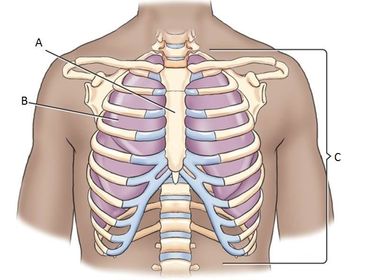

A. sternum B. lung C. 12 pairs of ribs